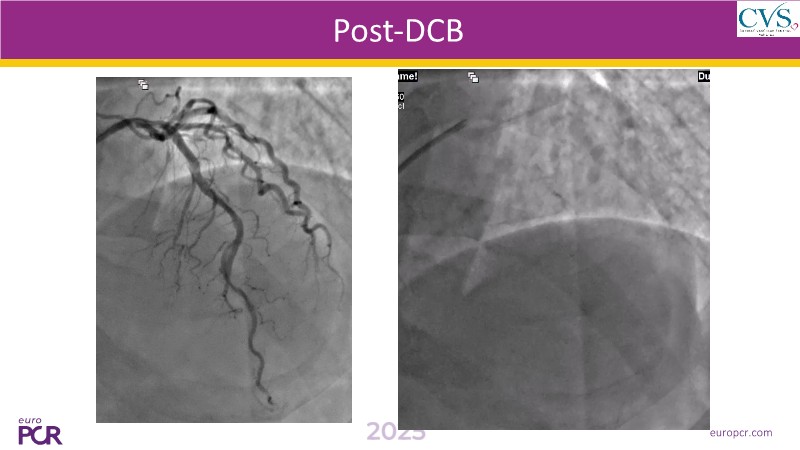

Discover how the next-generation RevoEdge high-pressure cutting balloon is transforming PCI with innovative design and proven clinical outcomes. This session presents a multicenter randomised trial and real-world case discussions, showcasing RevoEdge’s effectiveness in tackling resistant, complex lesions—including long, tortuous, and fibrotic cases. Learn practical tips, tricks, and intravascular imaging insights to optimize lesion preparation and improve patient outcomes. Don’t miss this opportunity to see how RevoEdge helps you cut through challenges and conquer PCI complexities.

- To learn about the clinical benefits and tips and tricks of using RevoEdge high pressure cutting balloon in different types of complex lesions through case-based discussion